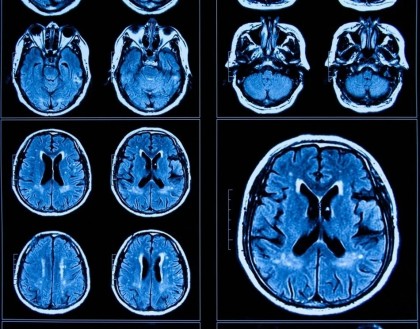

Studiul a inclus peste 160 de adolescenți, majoritatea de sex feminin, grupați în mai multe cohorte egale, care au raportat singuri simptomele depresive sau de anxietate cu care se confruntau. Participanții la studiu, din una dintre cohorte, au fost supuși unor evaluări imagistice ale creierului, pentru a obține grosimi corticale și măsurători subcorticale. Valorile obținute au fost utilizate de către cercetători pentru a calcula vârsta creierului și pentru a compara ulterior diferența de vârstă a creierului pentru toți participanții la studiu, prin utilizarea unui model bazat pe învățarea automată specific sexului.

În urma comparației frecvenței și a intensității simptomelor raportate de către participanții, cercetătorii au descoperit că probabilitatea respondenților de a raporta simptome mai severe de anxietate sau depresie a fost mai mare în grupul celor intervievați după pandemie. De asemenea, acești participanți au avut o grosime corticală bilaterală redusă, precum și volume mai mari ale amigdalei bilaterale și hipocampului, semne de îmbătrânire ale creierului.